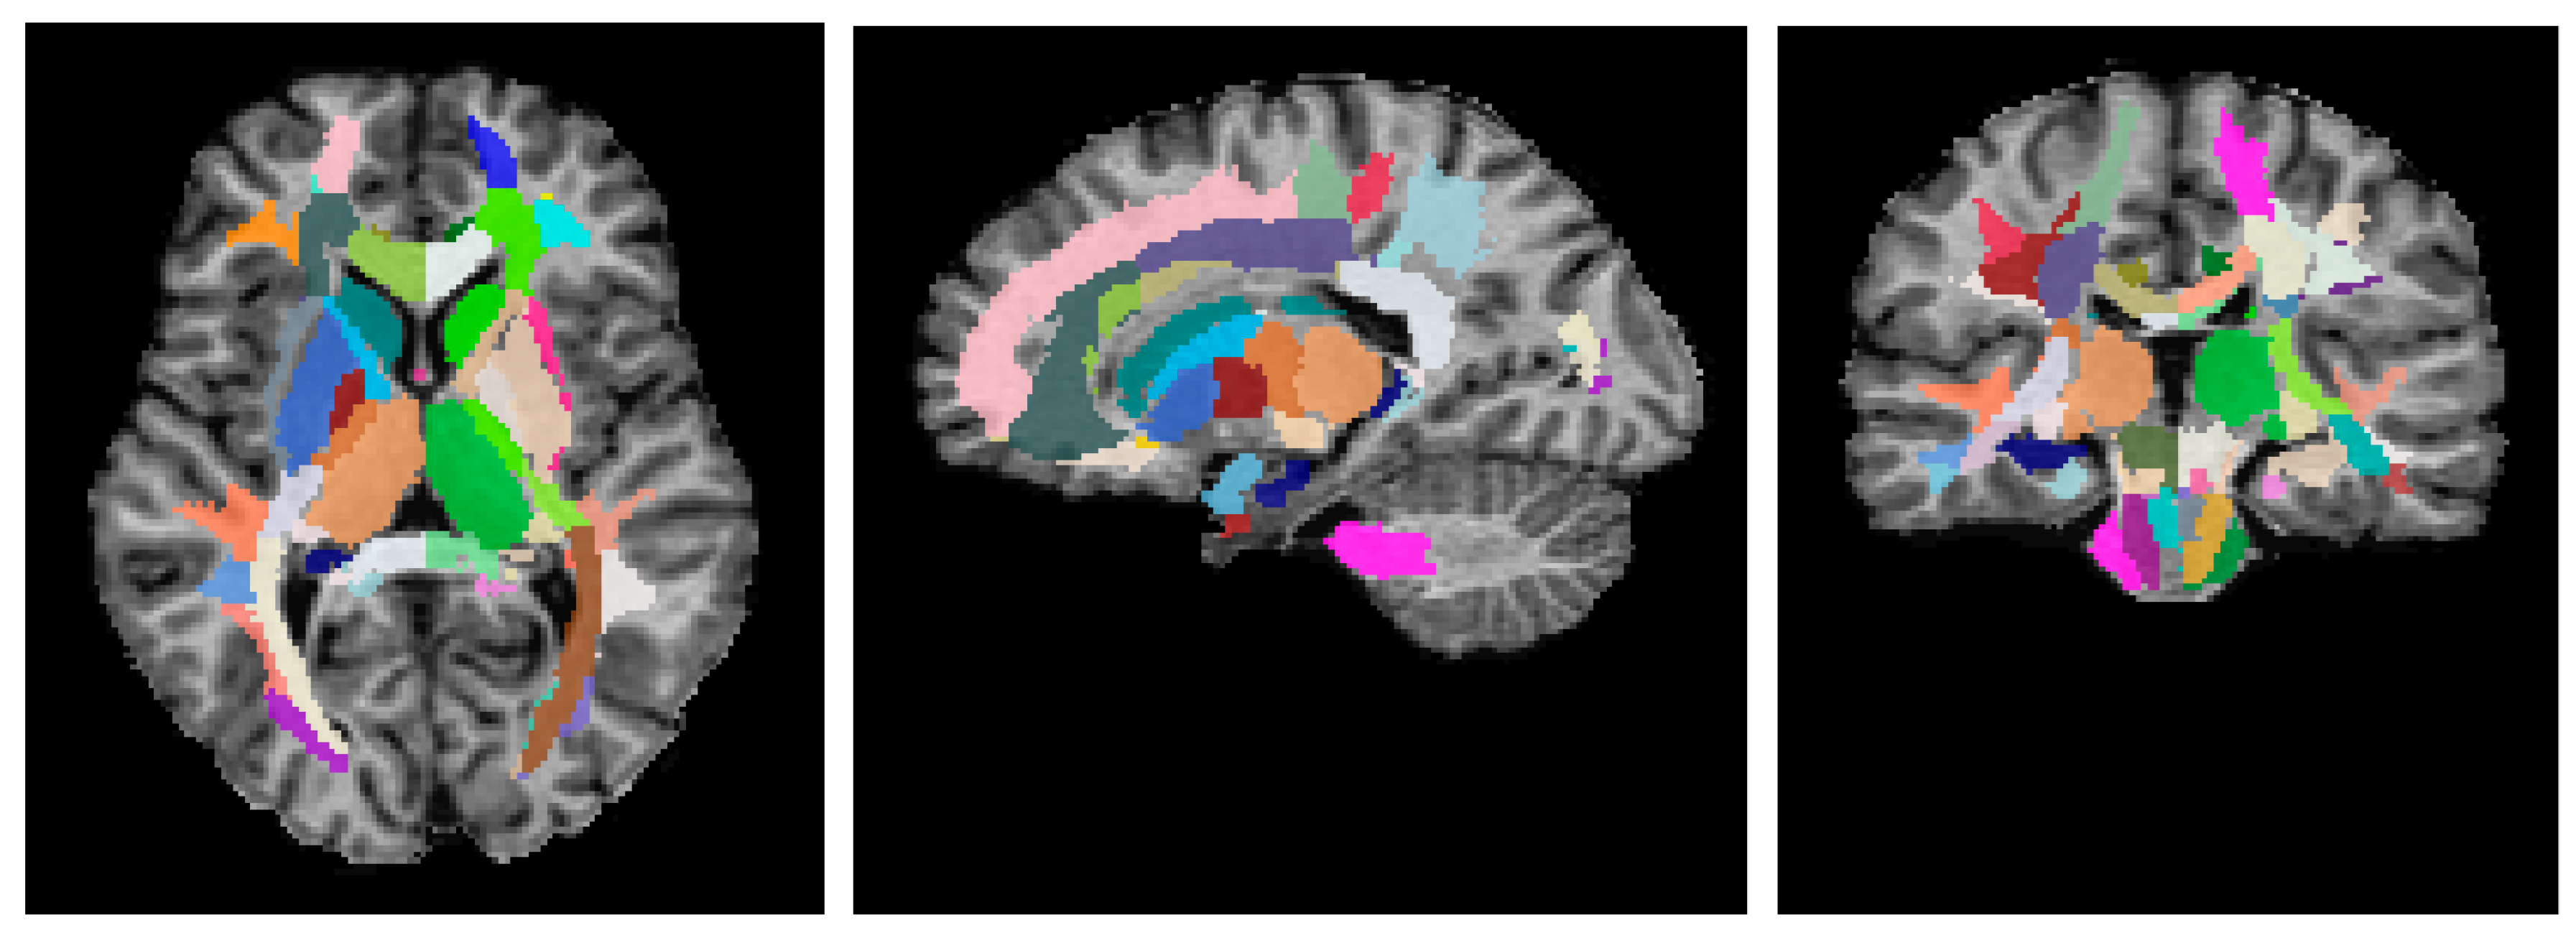

- WM Pathways and Fasciculi: (1) projection tracts—corticospinal tract (CST); anterior, superior, and posterior corona radiata (CR); anterior, posterior limb, and retrolenticular part of internal capsule (IC); cerebral peduncles; posterior thalamic radiation; medial lemniscus (ML); pontine crossing tract; inferior, superior, and middle cerebellar peduncles (CP). (2) Commissural tracts—genu, body, and splenium of corpus callosum (CC); fornix (FX) (stria terminalis, column, and body); tapetum. (3) Association tracts—superior longitudinal (SL) fasciculus; superior (SFOF) and inferior fronto-occipital (IFOF) fasciculi; uncinate fasciculus (UF); sagittal stratum; external capsule.

- Subcortical and Allocortical GM Structures: (1) allocortex—amygdala; hippocampus; entorhinal area. (2) Deep GM—caudate nucleus; putamen; globus pallidus; thalamus.

- Brainstem Structures: medulla; midbrain; pons.